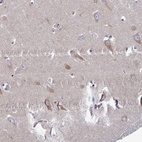

Immunohistochemical staining of human hippocampus shows moderate cytoplasmic positivity in neuronal cells.